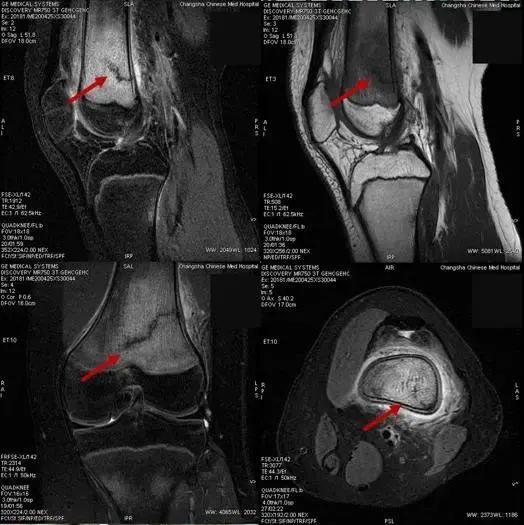

李政介绍,骨折一般分为创伤性骨折和病理性骨折两大类,应力性骨折又称“劳累性骨折”,属于创伤性骨折一类,也可以说是“报复性”运动损伤,既因为长时间不运动或运动量较少,突然增加超运动量或短期内增加大量的运动,肌肉耐力超过极限,肌肉协调能力下降,保护能力减弱,使部分肌肉、韧带损伤,而此时运动应力易集中某段骨骼,造成所谓的“应力性骨折”或“劳累性骨折”,长期减少运动本身也易使骨骼的韧性、强度减弱。应力性骨折通过普通X线片往往无法发现问题,容易发生漏诊,需要结合病史、查体,并配合磁共振检查来确诊诊断。